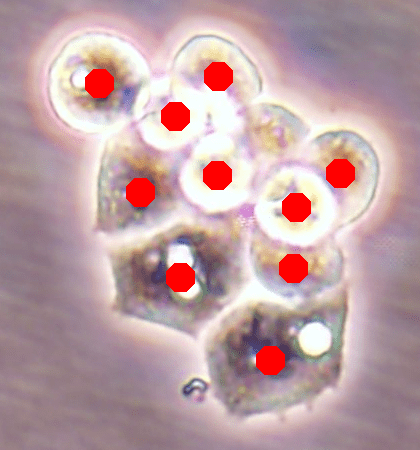

![]() |

| (a) | (b) |

| (c) | (d) |

For an example subimage given in Fig. 2a, these distance definitions are illustrated in Figs. 2b and 2c, respectively. The inner distance definition well indicates the cell centers since it uses the Euclidean distances from pixels to their closest cell centers. However, as it uses the centers as the reference point, the distance decrease from a center to its boundaries is the same for all directions and for all cells. Thus, when it is used alone, this definition imposes a circular and one-sized shape on the cells, as also seen in Fig. 2b. On the contrary, since the normalized outer distance is calculated with a reference to a cell boundary, this decrease may differ from one direction to another as well as from one cell to another, depending on the shape and size of the cell. Thus, it better preserves the morphological characteristics of cells, as seen in Fig. 2c.

The proposed DeepDistance model considers cell detection as a multi-task regression problem that estimates two distance maps from the RGB image, one for formulating the main task of cell detection and the other as an auxiliary task with the motivation of more effectively learning the main task. The FCN architecture given in the previous section is designed to learn these two regression tasks at the same time. This section discusses how this model can be extended to cover more auxiliary tasks, concurrent learning of which may further increase the performance of the main task. For this purpose, this section implements an extended version of the DeepDistance model that comprises an additional task of cell pixel classification. This additional task aims to construct a classification map (as shown in Fig. 2d) from the shared features of the encoder path111To take overlapping cells apart, and hence to obtain an improved map, cell boundaries are widen and subtracted from the classification map. This improved map is also used in the comparison methods to make fair comparisons.. Note that here, instead of defining another regression problem as the additional task, we use a classification problem in order to demonstrate that the model can easily be extended to cover the auxiliary tasks related with regression as well as classification.